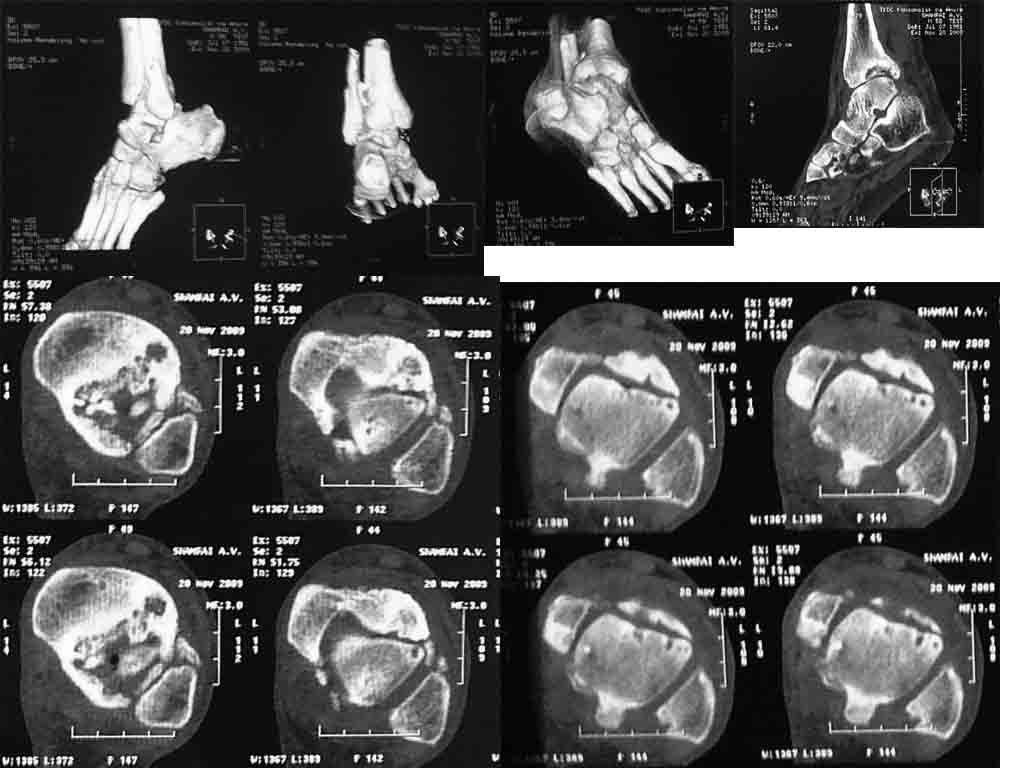

посттравматический асептический некроз

травма 2007 г., лечение консервативнопрошу помощи в выборе оперативного пособия.

пациент 58 лет, соматически стабилен, платёжеспособен.